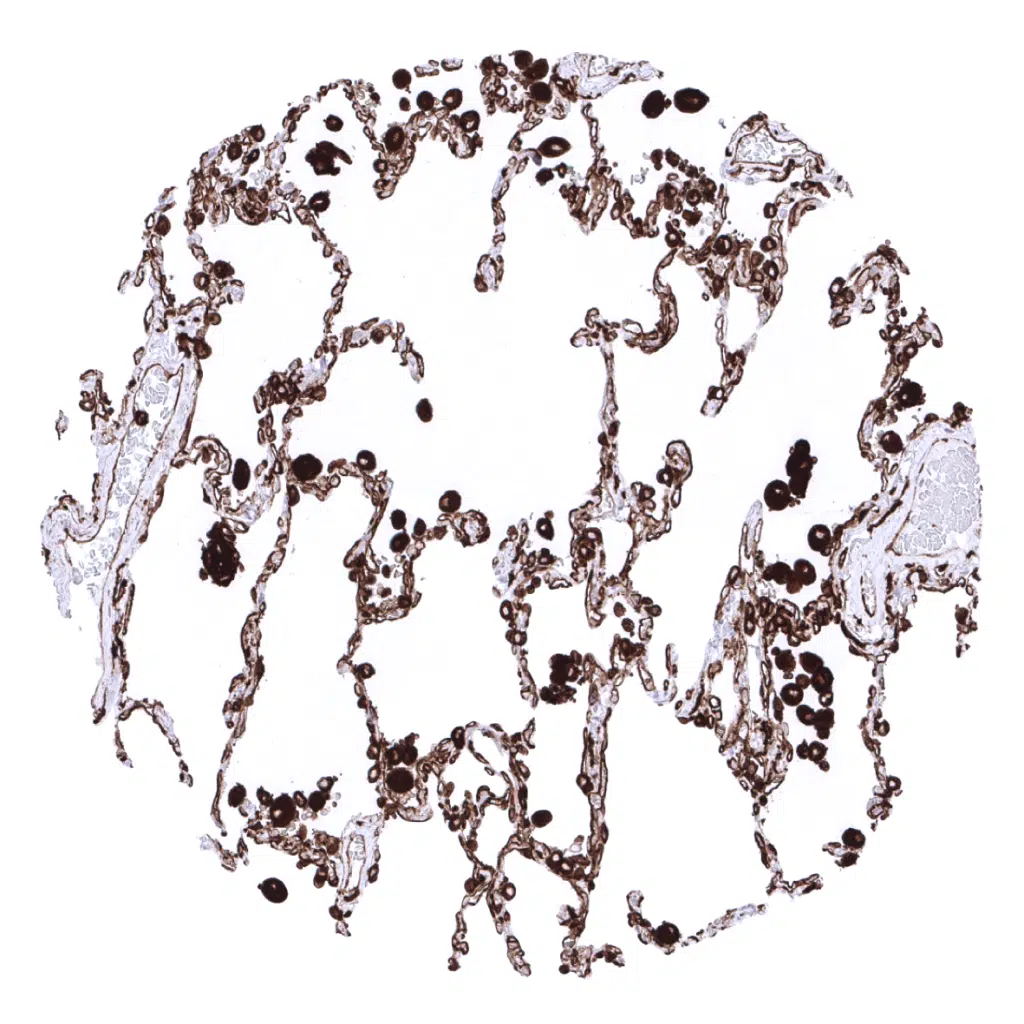

Lung: Intense HLA-DRa immunostaining of alveolar macrophages and alveolar capillaries.